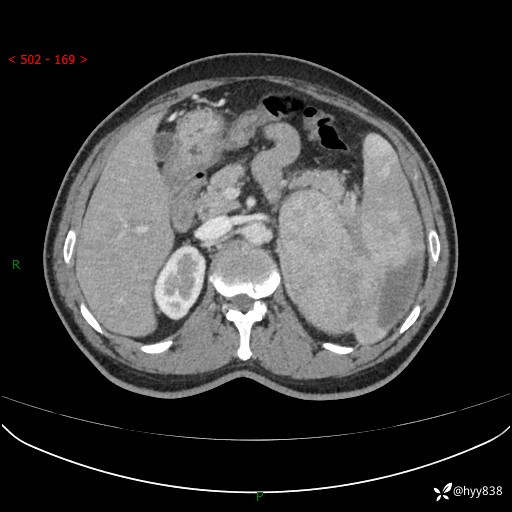

上腹部CT平扫

增强(动脉期+静脉期)